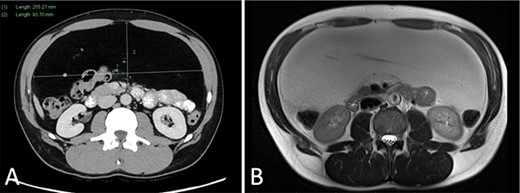

Abdominal ultrasound (US) revealed a well-demarcated, mildly hyperechogenic mass lesion apparently occupying the left lobe of the liver and measuring 6 × 25 × 24 cm. Both contrast-enhanced computed tomography (CT) and magnetic resonance imaging (MRI) demonstrated a well-circumscribed lipomatous mass within the greater omentum, measuring 9 × 24 × 27 cm, without discrete enhancing soft tissue components or local invasive features (Fig. 1). There were several foci of internal coarse calcification on CT corresponding with areas of low T1 and T2 signals and thin peripheral rim enhancement on MRI suggestive of focal fat necrosis. Intra-abdominal mass effect was evident but without acute complications. No metabolically active disease was demonstrated on fluorodeoxyglucose positron emission tomography (FDG-PET) (Fig. 2).

(A) CT portal venous phase axial slice demonstrating a well-circumscribed lipomatous lesion within the greater omentum measuring 9 × 26 × 24 cm; (B) MRI T2-weighted axial slice demonstrating intermediate T2 signal of the lesion.